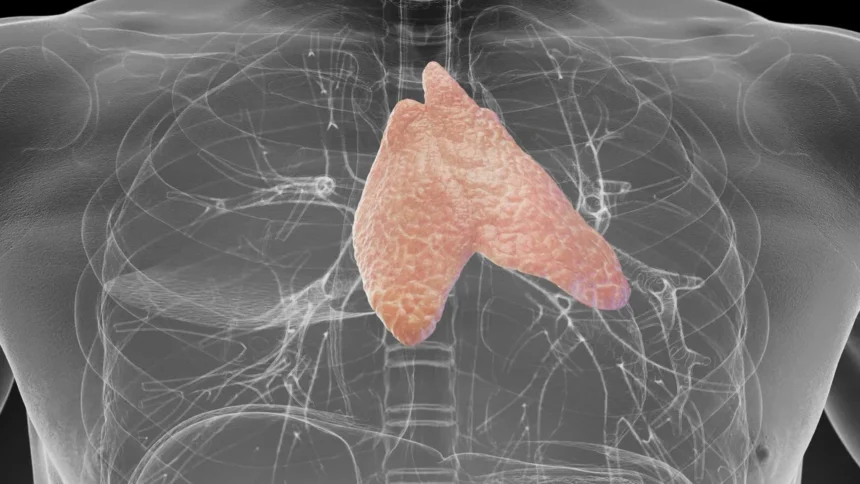

Január elején jelent meg a Harvard Medical School és a Massachusetts General Hospital közös kutatása, amely alapjaiban kérdőjelezi meg a csecsemőmirigyről (thymus) kialakult évtizedes orvosi konszenzust. A szegycsont mögött elhelyezkedő, apró szerv eltávolítása közel háromszorosára növelte a halálozási arányt, és jelentősen megemelte a rák kialakulásának esélyét. Ez a felfedezés új megvilágításba helyezi az immunrendszer működését és a daganatos betegségek megelőzését egyaránt.

A thymus az immunrendszer egyik alapköve, ahol a T-sejtek megtanulják megkülönböztetni a saját és az idegen sejteket. Pubertás után a szerv zsugorodni kezd, és az orvostudomány hosszú évtizedeken át úgy vélte, hogy felnőttkorban elveszíti jelentőségét. A fitbook.de által ismertetett legújabb eredmények azonban ezt komoly tévedésnek bizonyítják. A Heinrich-Heine-Universität Düsseldorf kutatói 2025-ben speciális immunsejteket azonosítottak a thymusban, amelyek közvetlenül képesek elpusztítani daganatos sejteket. A legmeglepőbb, hogy ezek a sejtek nem kapcsolnak ki a rákos sejtek hatására, így hatékonyabban támadhatják a tumorokat más immunsejtekhez képest.

Egy nagyszabású vizsgálat szerint azok, akiknek egészségesebb a csecsemőmirigyük, 50 százalékkal kisebb eséllyel halnak meg idő előtt. A szívhalál kockázata 63 százalékkal, a tüdőrák kialakulása pedig 36 százalékkal csökken náluk. A szakértők thymus-egészségi pontszámot dolgoztak ki az immunrendszer állapotának felmérésére. A kutatások rámutattak: a dohányzás, az elhízás és a krónikus gyulladás egyaránt gyengíti a szerv működését, közvetve növelve a súlyos betegségek kockázatát.

A thymus évtizedeken át alábecsült szerv volt, pedig kulcsszerepe lehet abban, ki mennyire marad egészséges idősebb korban. Az új felfedezések azt üzenik: nem csak a szívre vagy vércukorra kell figyelni, az immunrendszer láthatatlan részei is döntőek. Ez a kis szerv segíthet jobban megérteni és megelőzni a rák kialakulását a jövőben.